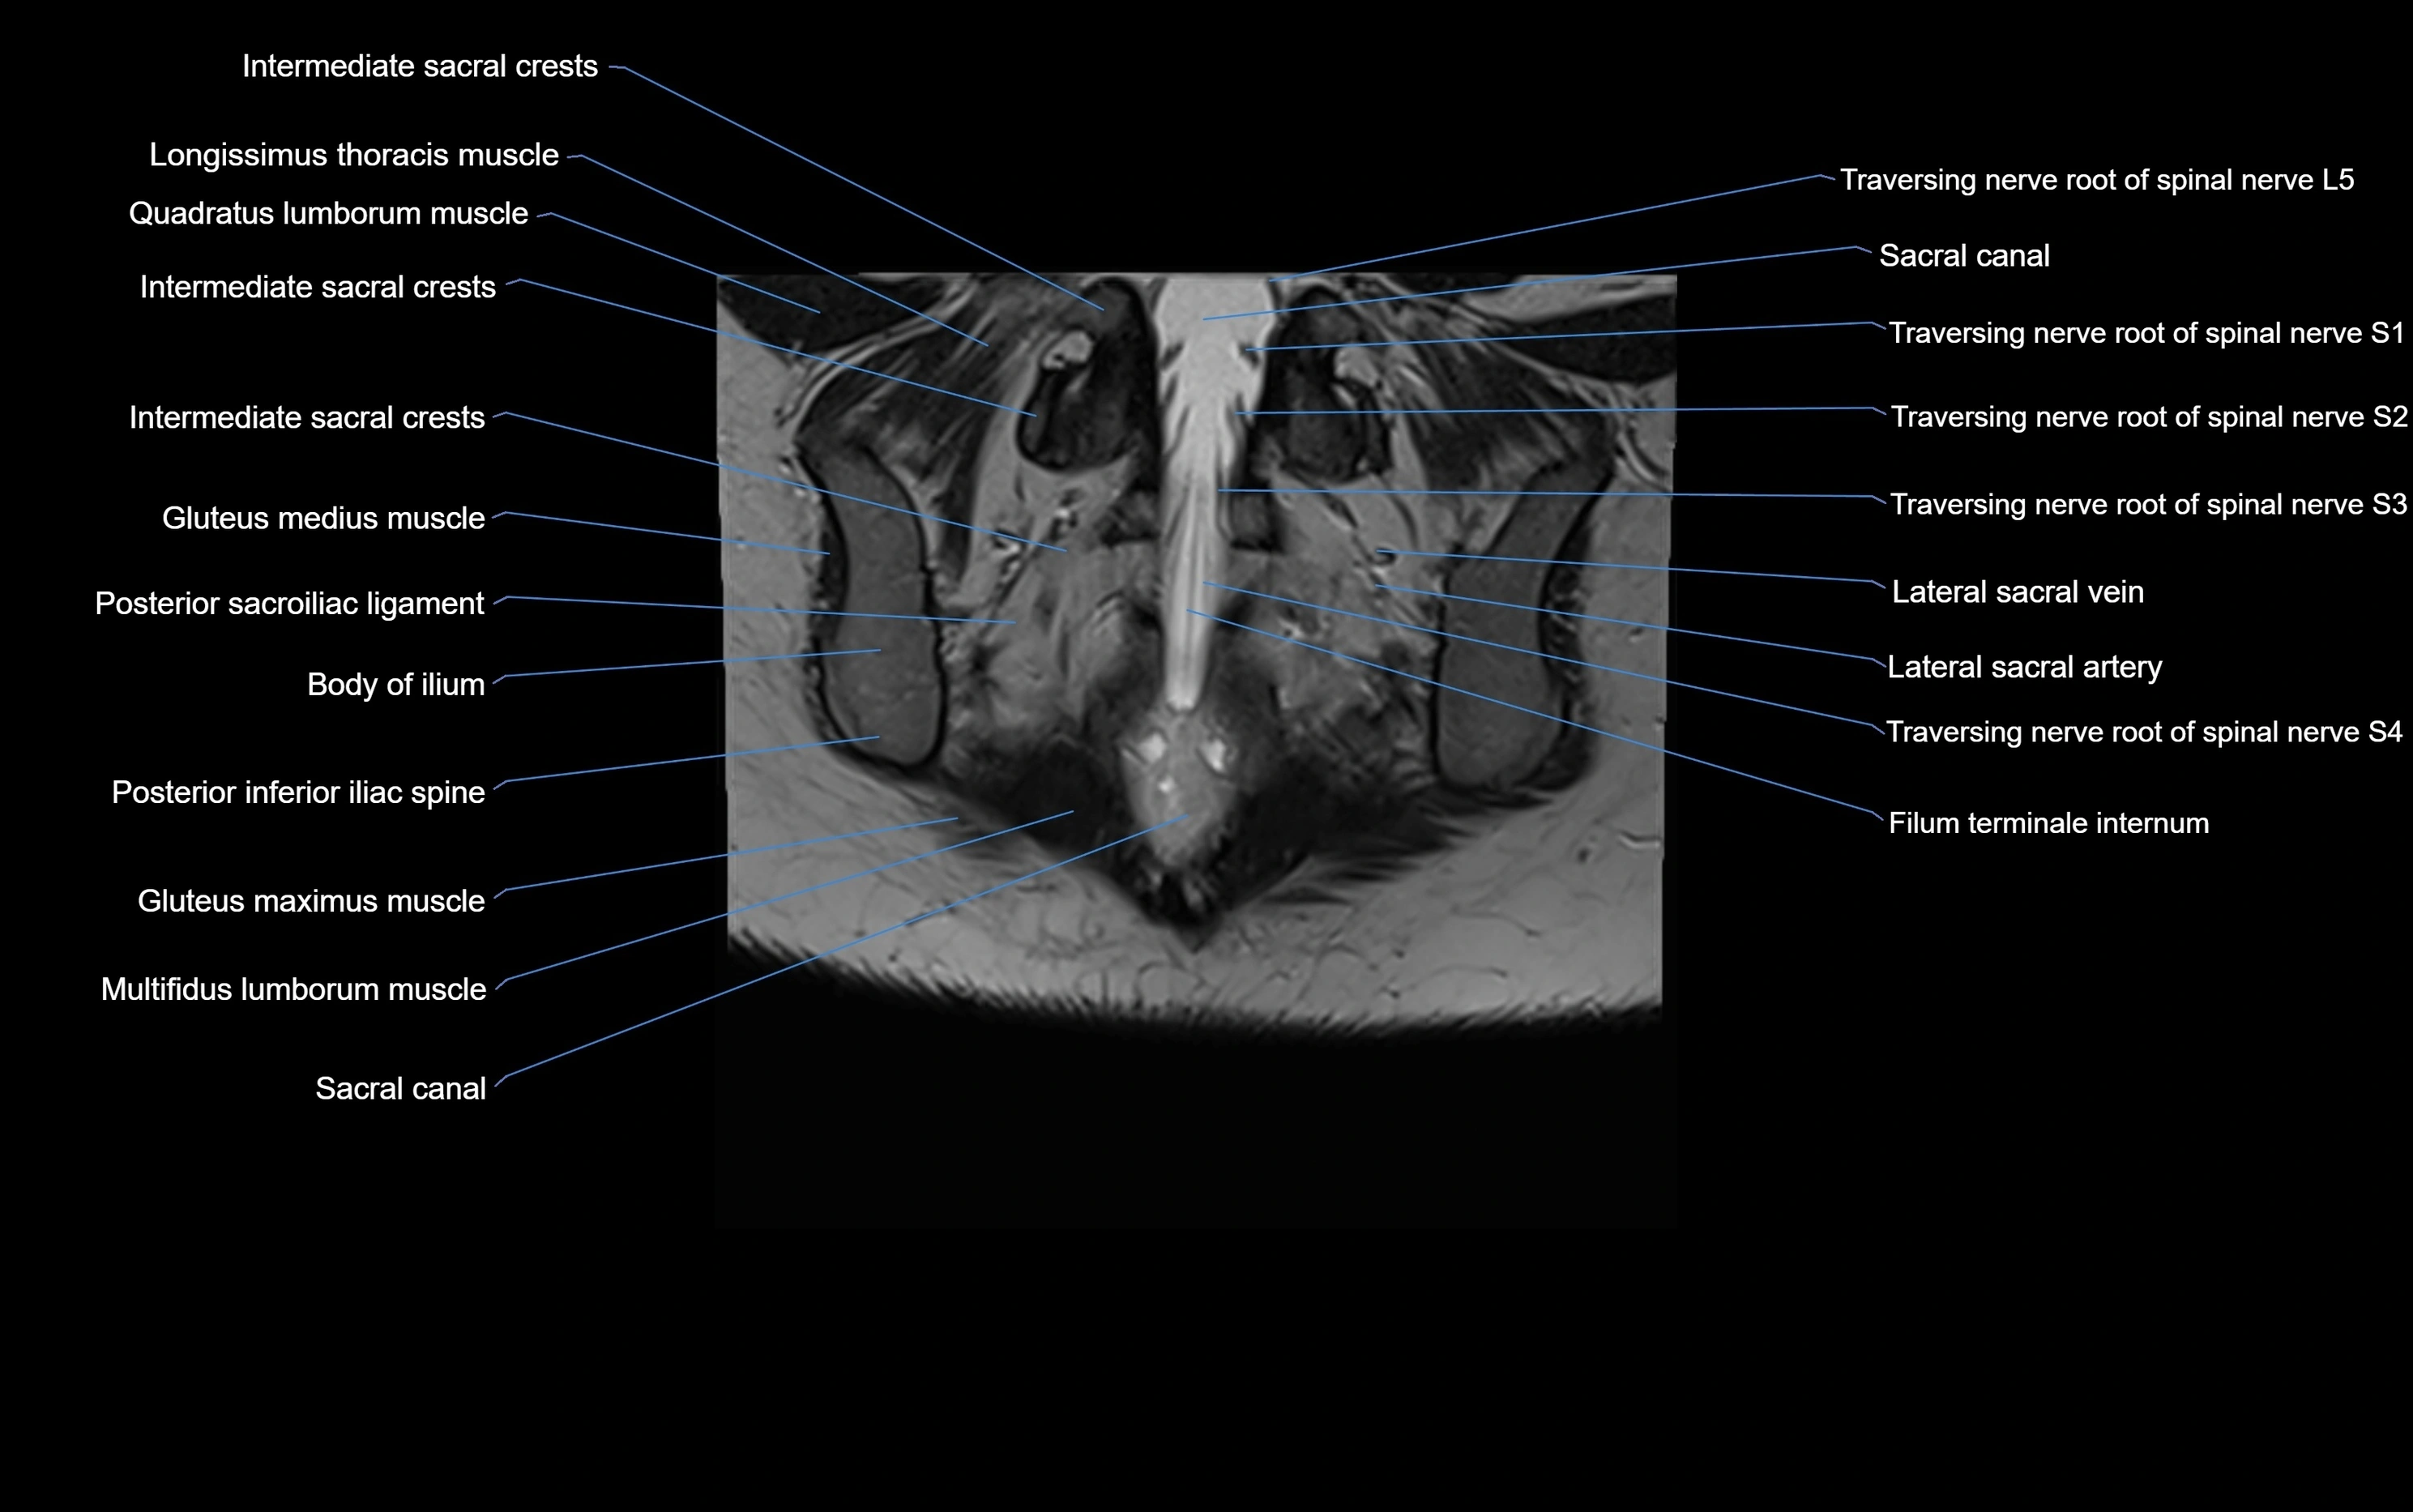

CT image

image